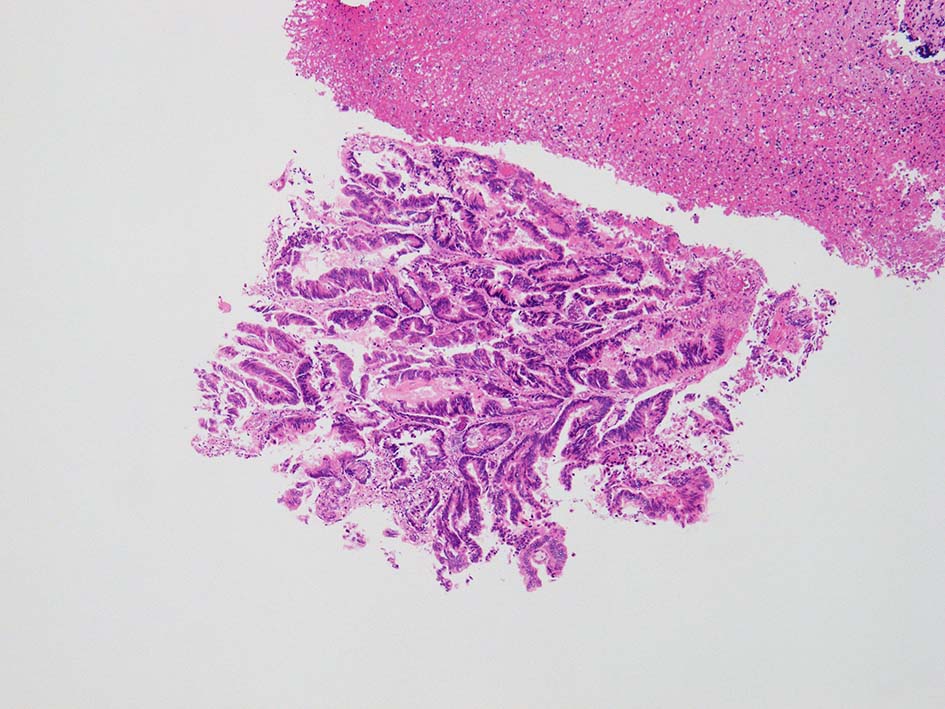

neutrophilic exudate の付着する腸管型腺癌部分. 核はより腫大し円形、vesicularとなっている. 上記腸管型とはCK20, CK7のそまりが異なっていた. 変性のためかもしれない.